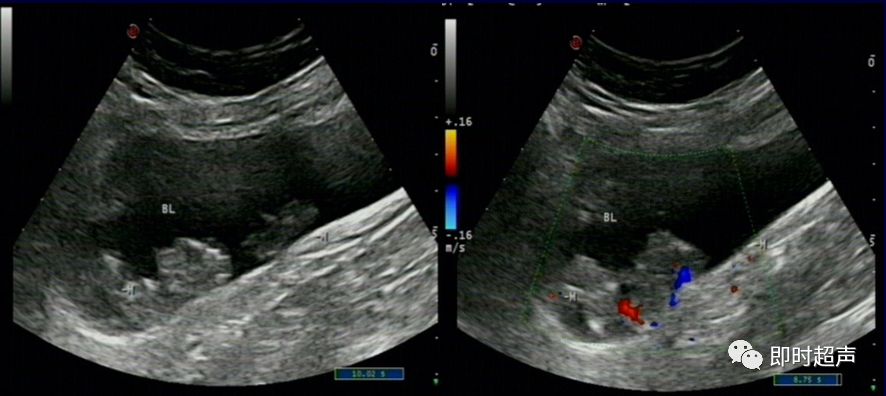

输尿管*尿喷**现象

(膀胱三角区、膀胱后壁两侧可见输尿管开口,排尿时可见输尿管口*尿喷**现象,尿流自后方斜向对侧前方,有断续光点移动。CDFI:显示尿流呈红色或橘红色。)